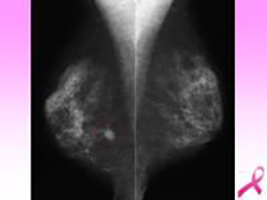

乳腺超音波検査 【3,850円】※女性のみ

中央の黒い不整な乳腺組織がたくさん残っている方におすすめ

乳房の超音波検査を行います。乳腺組織がたくさん残っている方におすすめです。乳腺超音波では、マンモグラフィでは見えにくい、柔らかい組織や小さなしこりを超音波で詳細に検査することができます。